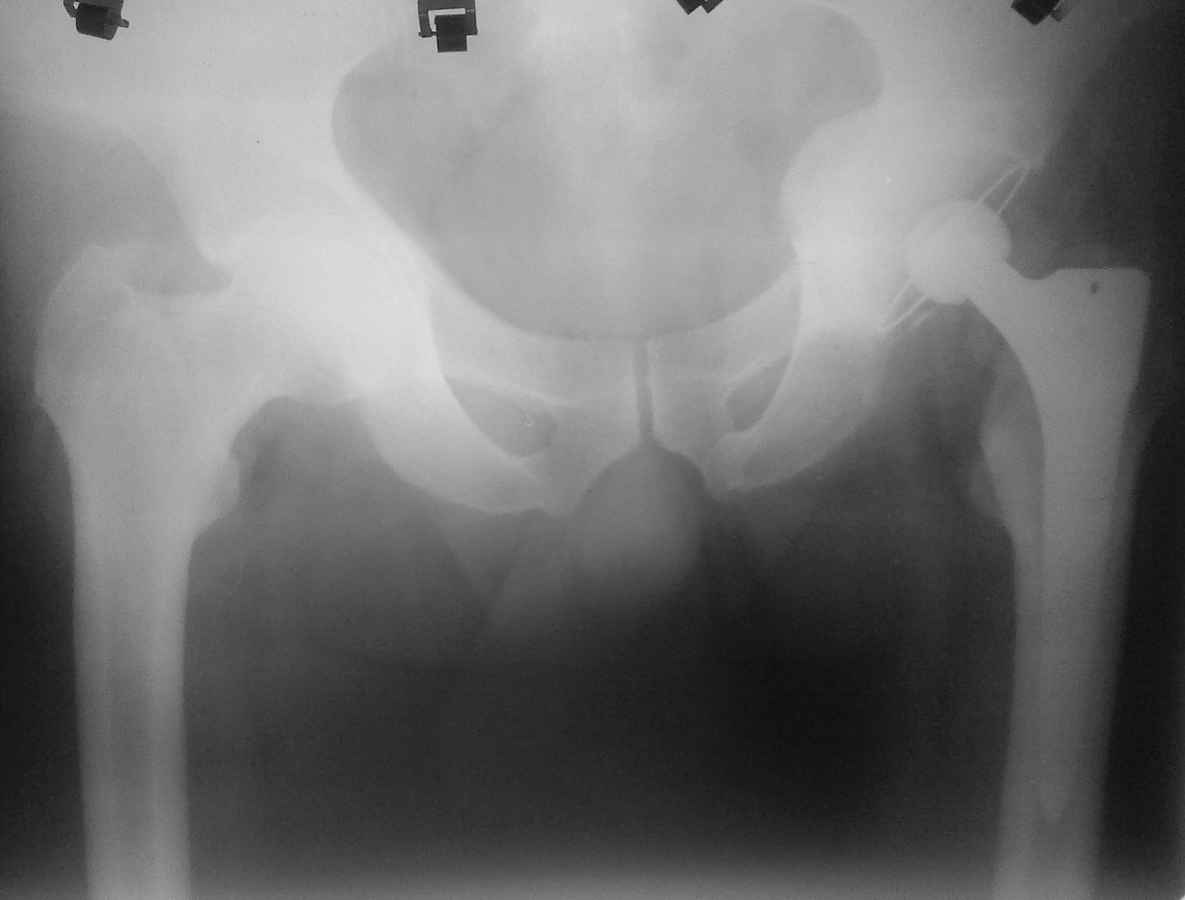

Здравствуйте. Уважаемые коллеги, поделитесь опытом у кого какая тактика при протрузионных

коксартрозах. У нас в клинике принято выполнять костную пластику дна стружкой из гололки, а

потом цементную чашку (снимки прилагаю). Выскажите свои взгляды на эту проблему,

пожалуйста.